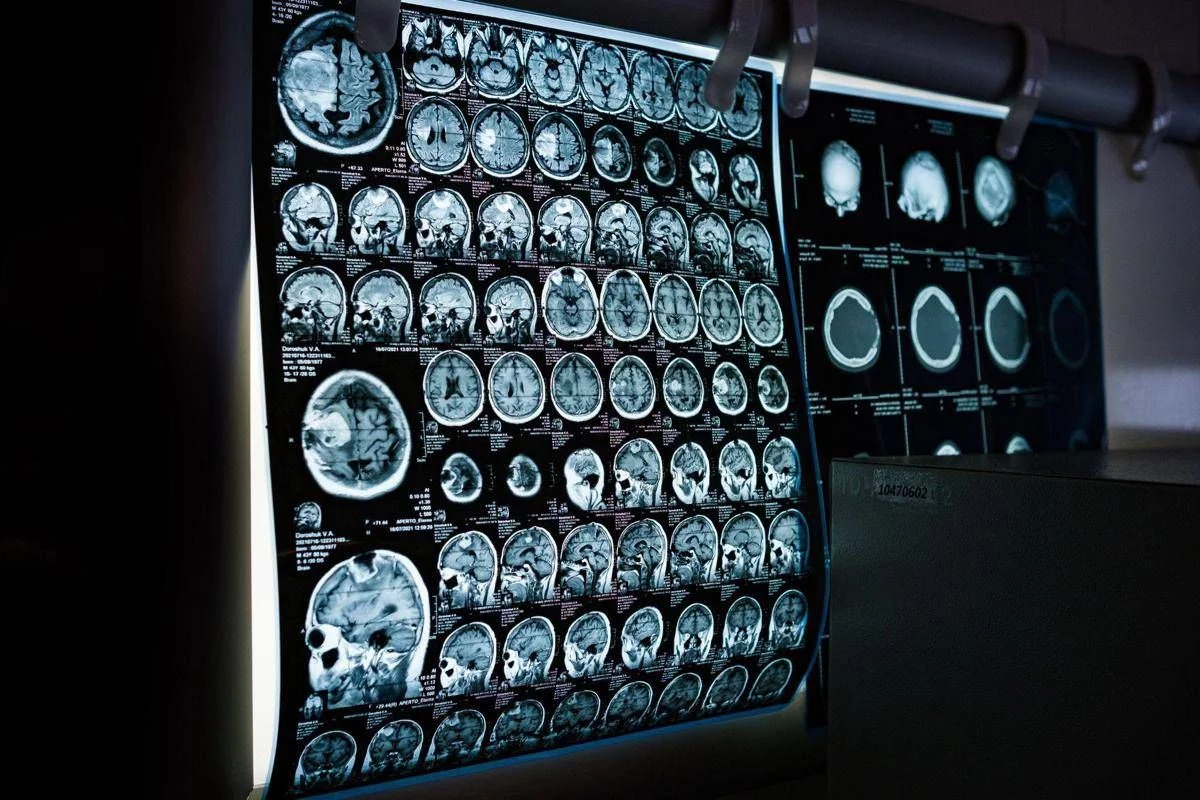

Un elemento centrale per migliorare la gestione delle malattie neurologiche rare – secondo gli esperti – è rappresentato dalla standardizzazione dei percorsi diagnostico-terapeutici, attraverso raccomandazioni condivise, algoritmi clinici e strumenti operativi che possano supportare il neurologo nella pratica quotidiana, anche al di fuori dei centri altamente specialistici. “Le malattie neurologiche rare, in particolare quelle di origine genetica, richiedono competenze specialistiche ma anche un approccio strutturato e condiviso”– sottolinea Massimiliano Filosto, coordinatore del Gruppo di studio Sin di Neurogenetica clinica e malattie rare – Il lavoro del Gruppo di studio è orientato alla definizione di best practices, allo sviluppo di algoritmi diagnostici e gestionali e alla formazione dei neurologi. Ridurre il ritardo diagnostico significa oggi offrire ai pazienti un accesso più tempestivo alle cure”.

Negli ultimi anni, il panorama delle malattie neurologiche rare è stato profondamente trasformato dalla disponibilità di terapie innovative che stanno cambiando in modo concreto la storia naturale di alcune patologie. Tra queste rientrano, a titolo di esempio, le terapie enzimatiche sostitutive, le terapie di riduzione del substrato, gli oligonucleotidi antisenso, le terapie geniche e altre strategie avanzate attualmente in sviluppo clinico. Questi approcci terapeutici, già disponibili o in fase avanzata di sperimentazione per diverse condizioni neurologiche rare – illustrano i neurologi – rendono ancora più urgente una diagnosi tempestiva e una corretta stratificazione clinica dei pazienti. In molti casi, infatti, l’efficacia delle terapie è strettamente legata alla precocità dell’intervento e alla preservazione delle funzioni neurologiche residue.